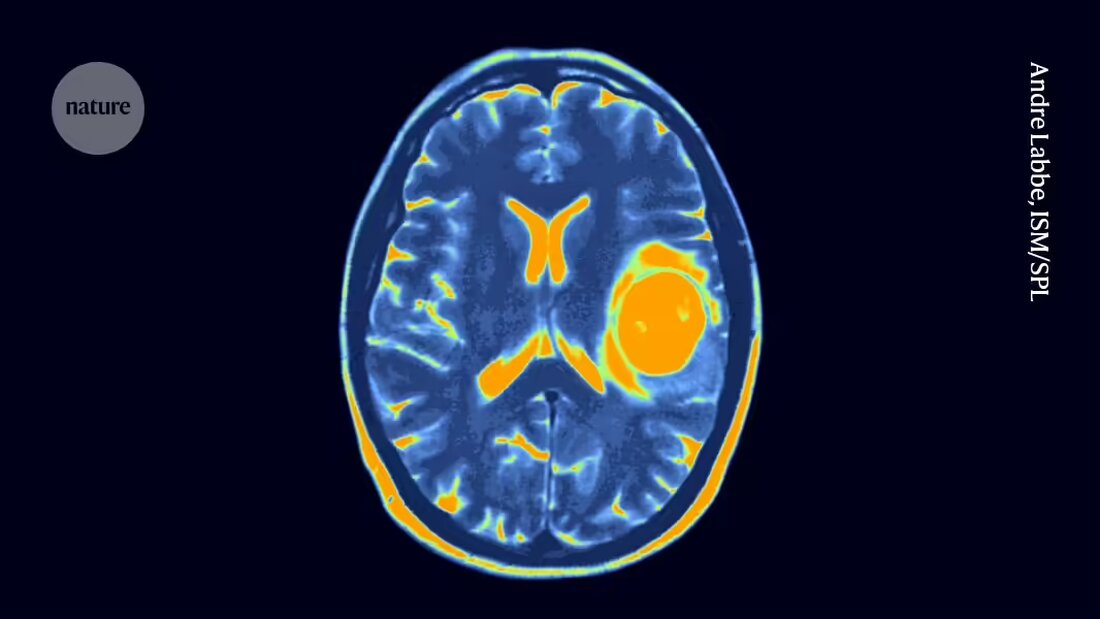

Trotz anhaltender Sicherheitsbedenken hat sich der Ansatz als erfolgreich bei der Behandlung mehrerer Blutkrebsarten erwiesen und in einigen Fällen langanhaltende Remissionen von mehr als einem Jahrzehnt hervorgerufen. Die Anwendung von CAR-T-Zelltherapien zur Behandlung von soliden Tumoren wie denen des Gehirns und der Lunge ist jedoch anspruchsvoller. Solide Tumoren können verschiedene Zellen mit unterschiedlichen Mutationen und unterschiedlichen Empfindlichkeiten gegenüber der Therapie enthalten. Solide Tumoren können auch für die T-Zellen schwieriger zu durchdringen sein.

Dennoch haben Studien an Mäusen darauf hingedeutet, dass CAR T-Zellen gegen diffuse Mittelliniengliome wirksam sein könnten. Neue Therapien für den Krebs werden dringend benötigt: Die Standardbehandlung besteht gelegentlich aus Strahlentherapie in Kombination mit Chemotherapie, aber der Krebs ist tödlich und die mittlere Überlebensdauer beträgt etwa 13 Monate nach der Diagnose, sagt Vitanza.